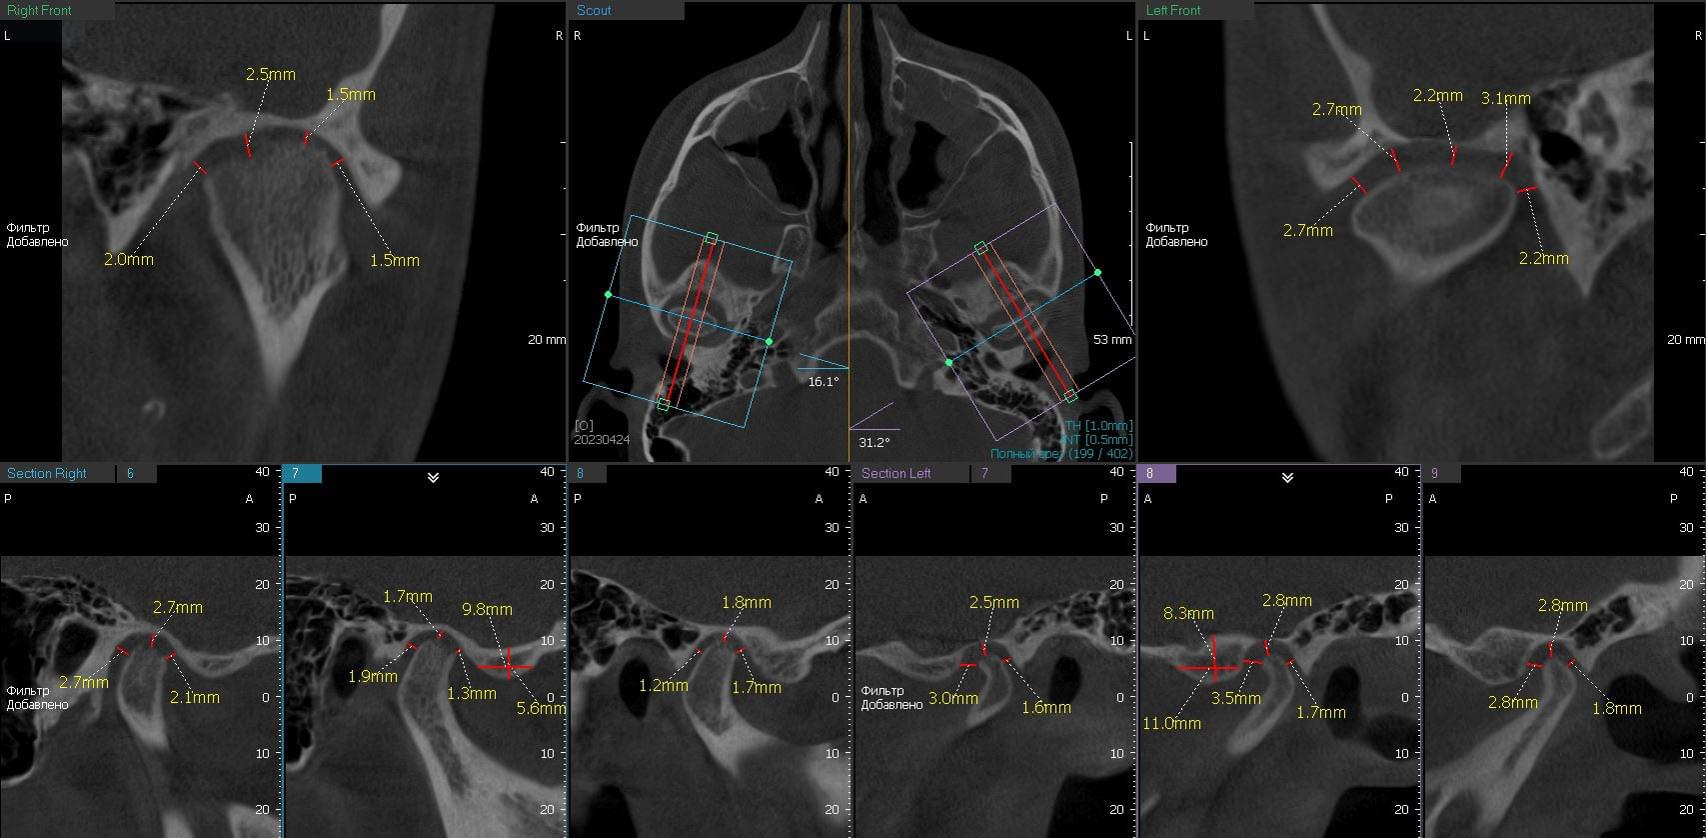

Pokud máte pochybnosti o svém temporomandibulárním kloubu, Myray Lab je tvoje spolehlivý Partner v diagnostice a identifikaci příčin této dysfunkce.Specializujeme se na provádění CT kloubů, lebek a okolních tkání, které nám umožňují podrobně vyhodnotit struktura a Funkce temporomandibulárního kloubu.

Jednou z hlavních výhod spolupráce s laboratoří je naše vysokoškolské vybavení, které Používá se v procesu CT.Používáme pokročilé technologie, které poskytují obraz vysoký vlastnosti a umožňují vám získat podrobné informace o stavu kloubu.Naše společnost Myray Lab použití inovativní metody a přístupy, které pomáhají našim klientům při přesné diagnóze a porozumění Problémy o jejich temporomandibulárním kloubu.

Zdraví našich zákazníků je naší prioritou, takže k každému nabízíme individuální přístup Pacient, který nás kontaktuje pro diagnostiku dysfunkce temporomandibulární kloubů.Náš Zkušení odborníci používají kombinaci klinické studie a CT skenování, aby to zjistili Příčiny příznaků a vyvinout účinný léčebný plán.